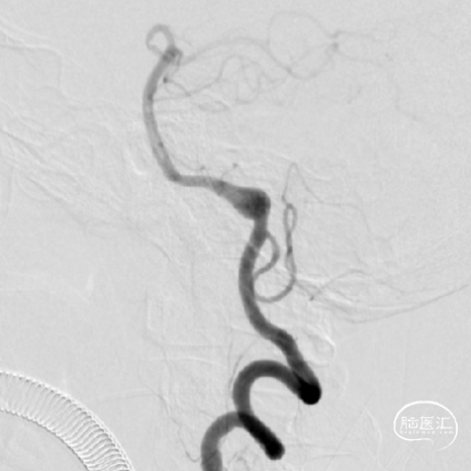

一位64岁男性,因间断胸痛3年入院心内科,入院后头颅CTA发现前交通动脉瘤,转我科继续治疗。既往有高血压,高血脂病史。体检无神经系统异常。

患者术前DSA

通过DSA检查在前交通处发现动脉瘤,立即用UKnow®动脉瘤稳定性评估,评估显示,该动脉瘤属于高风险,建议患者手术。通过风险评分,与患者沟通,患者表示同意手术,于是我们对其进行了动脉瘤栓塞术,愈后良好!